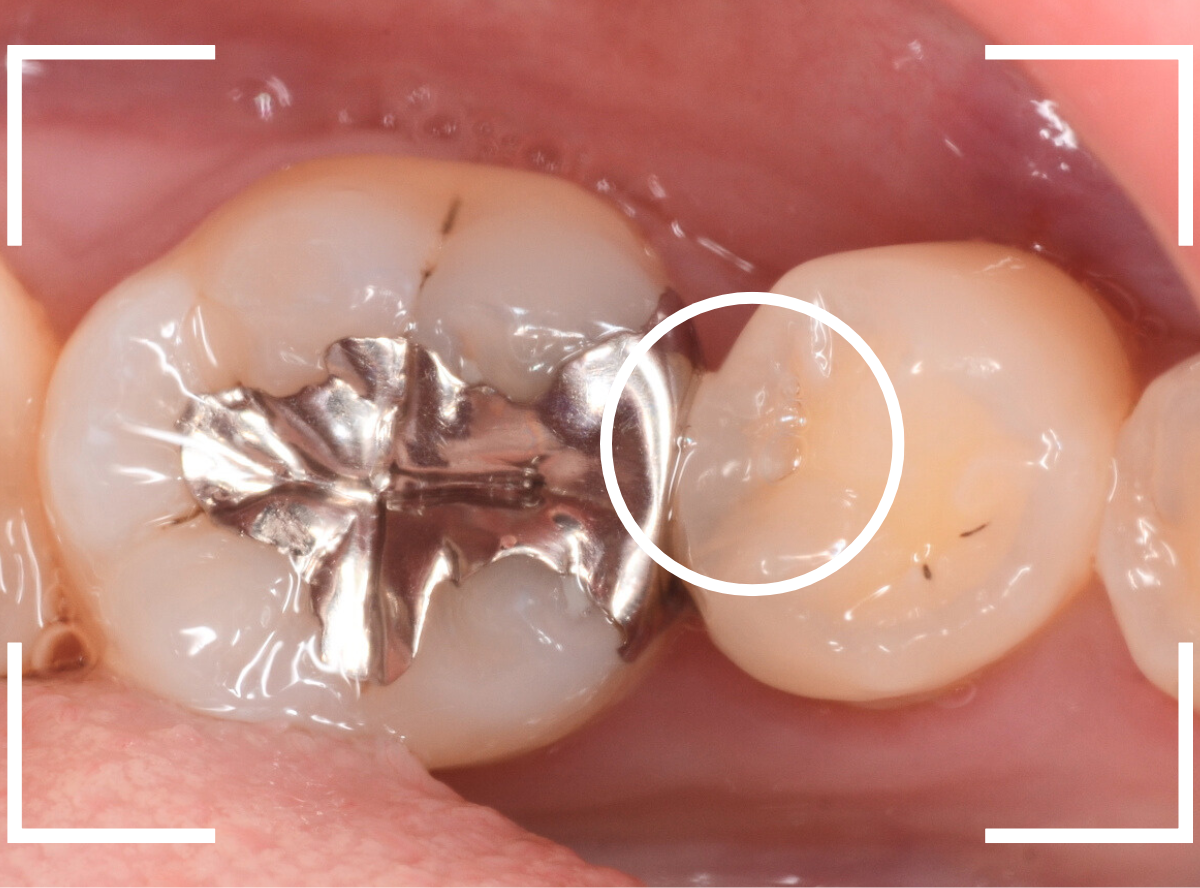

今回は、奥歯が神経に達する虫歯になってしまった患者さんのケースです。

隣りの歯とのすき間に大きな穴が空いているのが見えます。

レントゲン写真で確認します。

金属のつめものの下が、神経まで達する大きな虫歯になっています。

さて、神経の治療が終わり、歯の土台を作ったところで、手前の歯の側面にも虫歯が見つかり、治療を始めました。

手前の歯の虫歯も金属の中まで虫歯になっていました。

手前の歯の虫歯もかなり広い虫歯でした。